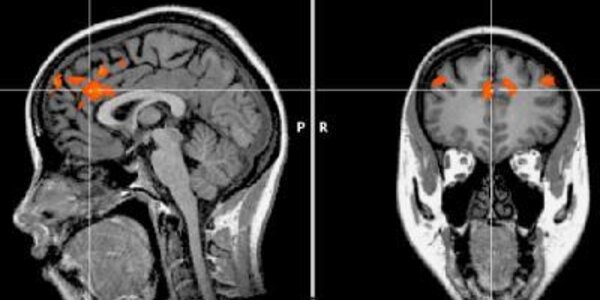

This Is What Your Brain Looks Like When You Lose Control

Self-control is a finite commodity.  Neuroscientists recently took a look at what happens when a person runs out of patience and loses self-control. This self-control, they say, is limited and once the supply has dwindled, we're less likely to keep our cool when a situation that requires self-control comes around. We have all seen people who lose it over 'nothing' and recognize it may be pent-up frustration. A study by University of Iowa neuroscientist William Hedgcockis the first to actually show that happening in the brain using fMRI images that scan people as they perform self-…